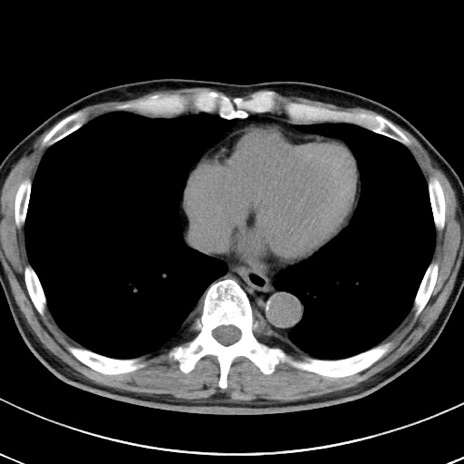

【腹部TIPS】症例29 参考症例 CT(横断像)

症例

70歳代男性